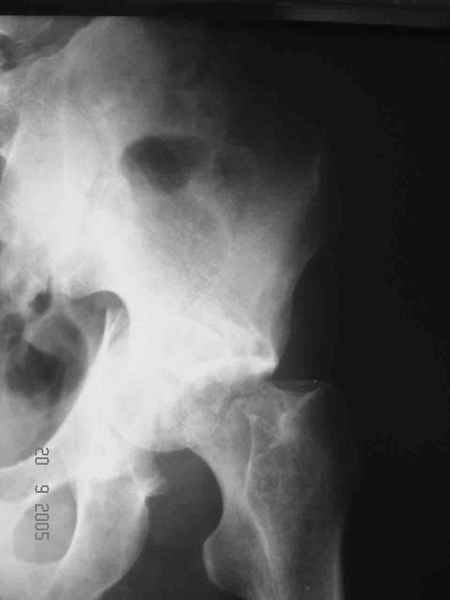

Больной 18 мая 2003 года в автоаварии получил перелом левой вертлужной впадины, вывих бедра. Госпитализирован в один из стационаров области.Вывих вправлен. В последствии бедро вывихивалось еще дважды. На консультацию был представлен снимок от 19.05.03г., больной переведен к нам 3.06.03г. Снимок при поступлении - перелом впадины, задне-верхний вывих бедра. 05.06.2003 г. выполнено открытое вправление вывиха левого бедра и остеосинтез стенки вертлужной впадины двумя винтами. Послеоперационный период без осложнений. Объем движений в левом тазобедренном суставе восстановился полностью. Выписан на амбулаторное лечение в удовлетворительном состоянии с рекомендациями 3 месяца ходить на костылях без нагрузки на оперированную конечность. На контрольных рентгенограммах левого тазобедренного сустава 13.10.2003 г. - признаки консолидации перелома; плотность, форма головки и состояние суставных поверхностей удовлетворительные. Разрешена дозированная осевая нагрузка, на конечность с использованием дополнительной опоры. 19.12.2003 г. больной обратился с жалобами на боли в левом тазобедренном суставе. На рентгенограммах левого тазобедренного сустава 19.12.2003 г., 20.02.04г. - асептичекий некроз головки бедра. 5.04.04г. - эндопротез. Сейчас ходит без трости, не хромает. Особенность эндопротезирования - при удалении винтов прослежена линия перелома заднего края впадины и предложено установить чашку несколько меньшего диаметра, чтобы она была покрыта несломанной частью.

Случай, представленный Вами, совсем не идентичен обсуждаемому. У Вашего пациента был поперечный перелом с переломом заднего края, а в обсуждаемом случае - высокий двухколонный перелом вертлужной впадины.

То есть в представленном Вами случае был перелом заднего типа, в нашем случае центрального. У Вашего больного был застарелый задний вывих, у нашего - перелом шейки. Столь раннее разрушение головки, вероятно, было во многом обусловлено тем, что не была достигнута анатомическая репозиция, головка бедра осталась смещенной кзади, что является частой ошибкой при крупных фрагментах свода.